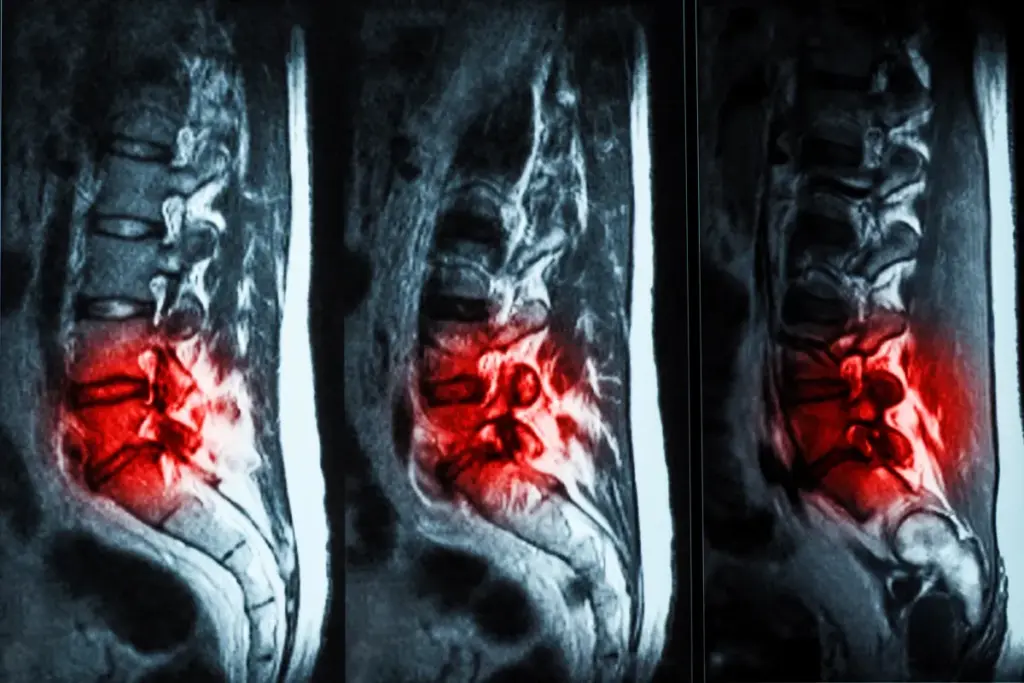

Understanding Degenerative Disc Disease

Let’s dive into degenerative disc disease and how it affects our spine. This condition impacts the spinal discs. These discs are key for shock absorption, spine flexibility, and support.

What Happens to Discs as They Degenerate

With age, our spinal discs start to break down. They lose water, becoming less flexible and more likely to crack. The outer layer can tear, causing the inner gel to bulge and irritate nerves, leading to pain.

As discs degenerate, they shrink, making the spine unstable. This instability can lead to bone spurs as the body tries to stabilize the area. This can cause more problems.